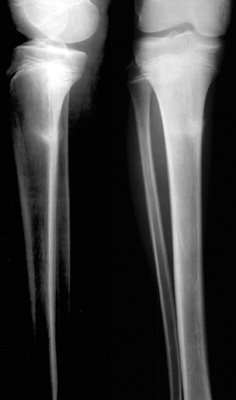

Proximal Tibial Stress Fracture

- Appears as a band of sclerosis in the proximal tibia on plain film.

The following radiograph was obtained from an athlete complaining of a painful shin.

Lateral and AP views